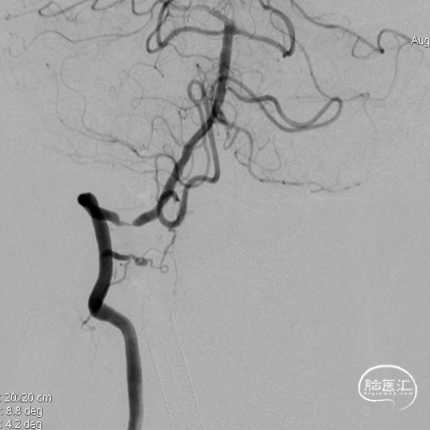

右椎动脉动脉正侧位:

病变情况分析:右桡动脉穿刺,置6F桡动脉鞘管,5F多功能导管在泥鳅导丝辅助下脑血管造影提示:右椎动脉V4段重度狭窄(约90%)。

泥鳅导丝携5F 115cm颅内支撑导管,至右椎动脉V2段。